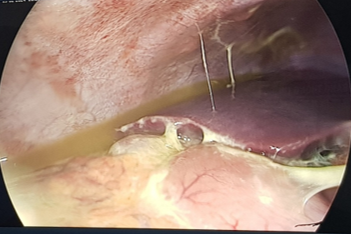

Polyp tại lỗ ruột thừa - một trường hợp hiếm gặp

11/17/2023 8:50:00 AM

Vừa qua, khoa Tiêu hóa Bệnh viện trẻ em Hải Phòng đã nội soi đại tràng, cắt gọn polyp kích thước 0,5 cm tại lỗ gốc ruột thừa, tránh cho bệnh nhân 14 tuổi ca phẫu thuật không cần thiết